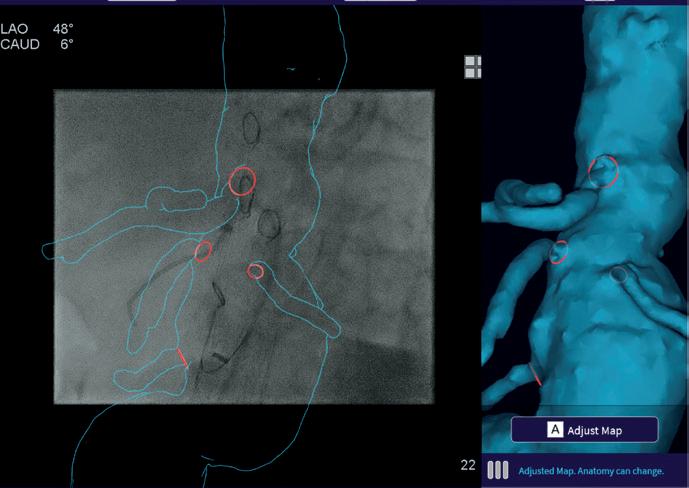

Image Tracking

The left image shows Image Tracking automatically overlaying the Map on the live X-ray fluoroscopy video on the left-hand side of the screen with a 3D rendering of the same Map on the right. The green color indicates that this is a Preoperative Map. The right image shows the same X-ray but with the Adjusted Map (blue color)

as a reference image. Image Tracking continues watching the live fluoroscopy on the left side until a new Map can be generated. When vessel deformation becomes apparent, for example with a digital subtraction angiography (DSA), the Cydar remote control can Adjust Map using Virtual Wires to straighten, bend, displace or rotate segments of the Preoperative Map to match the deformed anatomy.